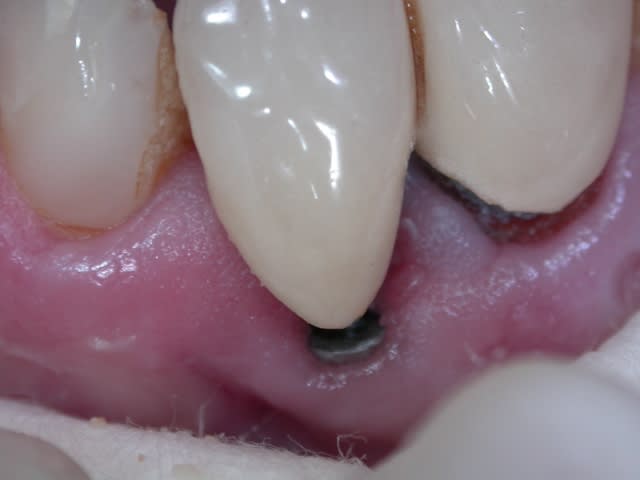

Comme je n'ai pas pu trouver la marque de l'implant, j'ai du me débrouiller autrement pour dépanner ce patient( à la cmu).

Voilà quelques photos de l'étape provisoire et du definitif avec un ancrage dans l'impant et des ailettes palatines.

Un grand merci à mon prothésiste.